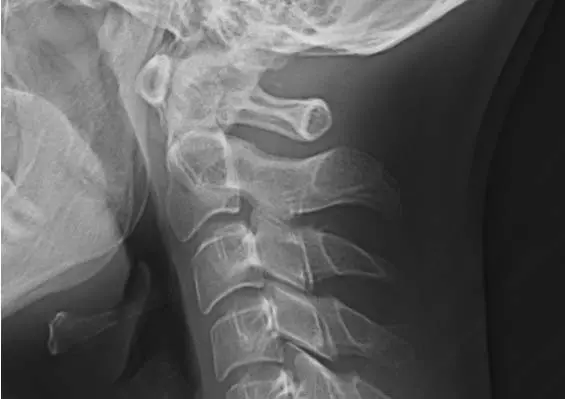

SZYJA SMARTFONOWA

Zespoły bólowe w zakresie narządu ruchu są coraz częściej obserwowane w społeczeństwie, nie tylko w grupie pacjentów starszych, ale również u młodzieży i młodych dorosłych. Poza typowymi dolegliwościami, jakimi są ból oraz ograniczenie ruchomości w zakresie objętego patologią narządu, pojawiają się inne symptomy chorobowe, które utrudniają codzienne funkcjonowanie, są trudniejsze do kontrolowania oraz leczenia. Należą do nich m.in. nudności, zawroty głowy, zaburzenia: widzenia, słuchu oraz równowagi. Objawy te mogą występować w przebiegu zespołu szyjno-głowowego, tzw. szyi smartfonowej.